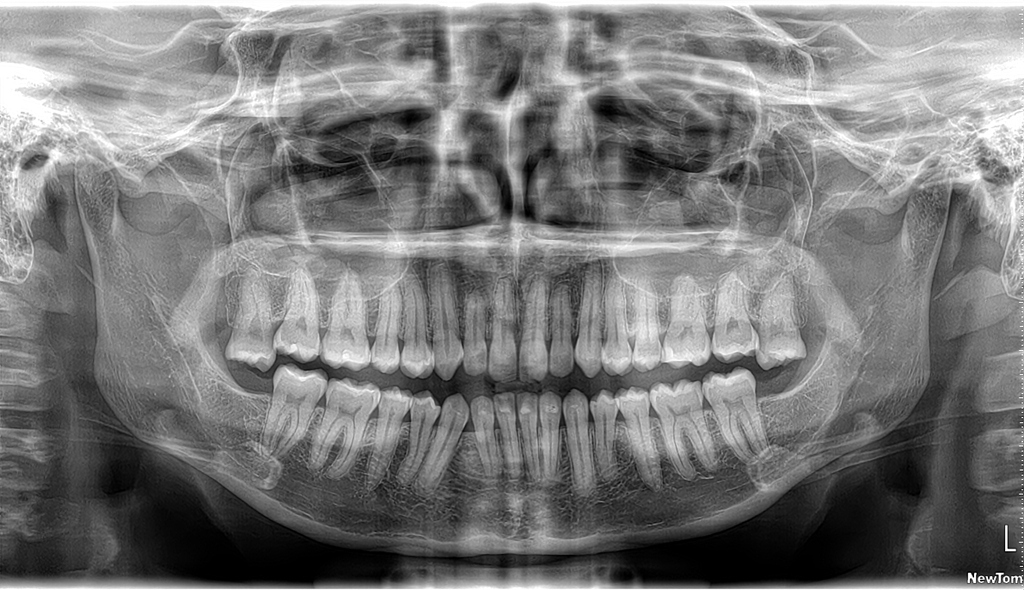

Realizamos estudios panorámicos dentales empleando la avanzada tecnología Newtom, reconocida en Italia y toda Europa.

Captura una vista completa de toda la boca en una sola imagen, útil para evaluar la estructura dental y el crecimiento de muelas del juicio.